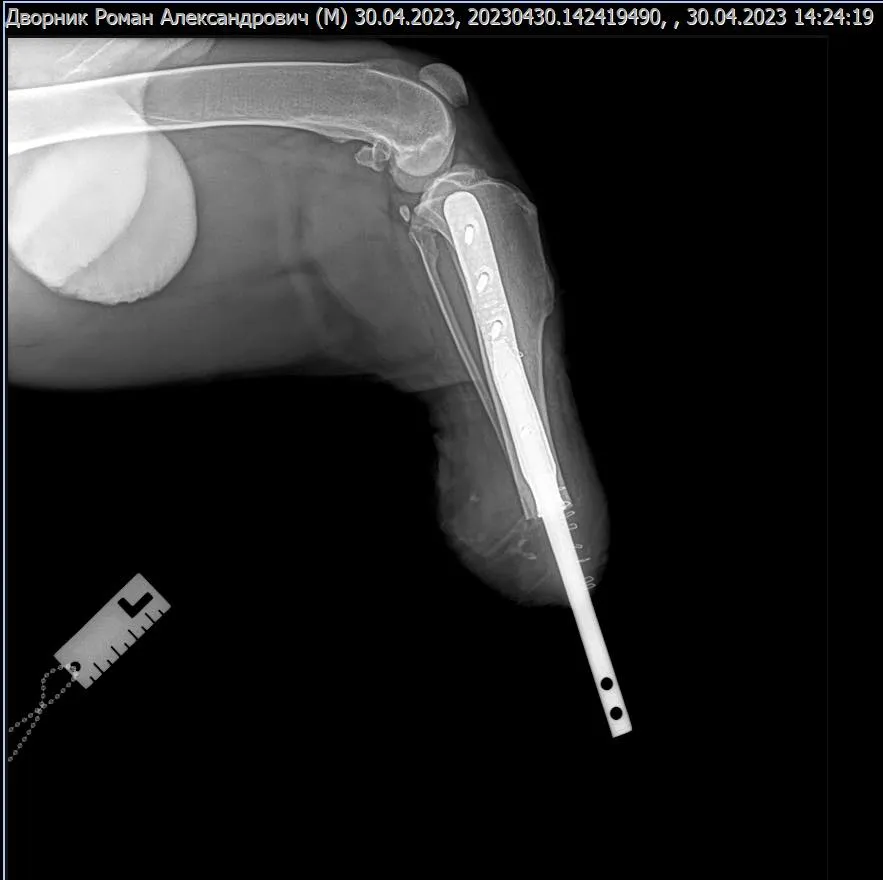

Лікарі Харківського ветеринарного шпиталю вперше провели операцію з біоінтегрованого протезування кінцівки у собаки. За словами головного лікаря шпиталю Віталія Клубаня, це пес породи російський чорний тер’єр, вагою 56 кг, який втратив лапу через російське бомбардування касетними снарядами під час прогулянки.

Спочатку собаку лікували в Києві, тому до харківських ветеринарів він потрапив уже із зашитими ранами. Сам імплант встановили на базі Салтівської ветеринарної клініки. Протез розробила українська компанія 3D Metal Tech, що виготовляє хірургічні імпланти із титанового сплаву методом 3D-друку.